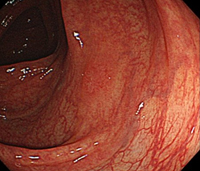

B:同部位の通常観察像。通常観察では発見困難である。

-

C:色素撒布像によって病変が明瞭化する。